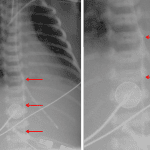

Age: 1 day (term)

Sex: Male

Indication: Line placement

Findings

- Left subclavian approach central venous catheter with tip projecting over the superior vena cava

- Endotracheal tube with tip projecting at the level of T3

- Enteric tube tip overlies the gastric body

- Umbilical arterial catheter loops back on itself at the level of T9

- Scattered patchy pulmonary opacities, most confluent in the left lung base

- Small left pleural effusion

Diagnosis

- Neonatal pneumonia

Left subclavian approach central venous catheter with tip projecting over the superior vena cava. No pneumothorax.

Endotracheal tube with tip projecting at the level of T3.

Enteric tube tip overlies the gastric body.

Umbilical arterial catheter loops back on itself at the level of T9. Consider repositioning to reduce the redundant distal coil.

Scattered patchy pulmonary opacities, most confluent in the left lung base, which in combination with a small left pleural effusion raise concern for pneumonia.